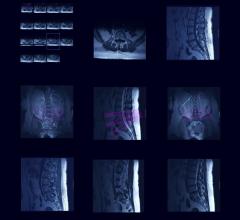

Value-driven health platform Spreemo has completed the first phase of a study to determine how interpretative variability in magnetic resonance imaging (MRI), a standard diagnostic test, can influence the course of a patient’s treatment.